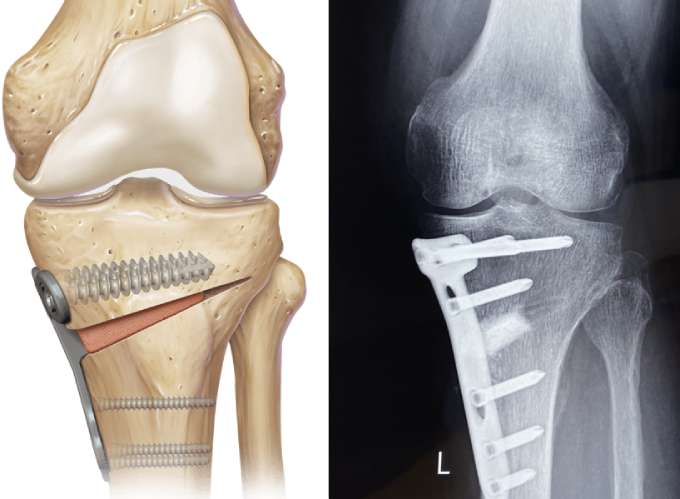

Высокая тибиальная остеотомия (ВТО) — это органосохраняющая ортопедическая операция, направленная на коррекцию оси нижней конечности и перераспределение нагрузки в коленном суставе. Метод позволяет уменьшить болевой синдром, замедлить прогрессирование артроза и отсрочить эндопротезирование. Вы можете подробно прочитать про операцию здесь: "Остеотомия большеберцовой кости - техника"